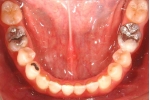

| 治療中

| マルチブラケット終了時